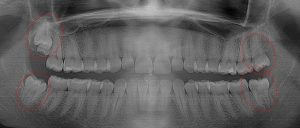

This 19 year old patient has all four 3rd molars present (circled). Only the upper left 3rd molar has fully erupted. The lower left 3rd molar is partially exposed and decaying while the lower right soft tissue impacted, both requiring extraction. Note the double crown on the upper right third molar.